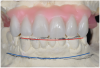

Fig 10. Surgical impression—Open-tray impression copings are secured and splinted with a denture-strengthening bar using low-expansion pattern resin.

Figure 10

Fig 11. Surgical impression—Modified plastic impression tray seated to verify that there are no interferences with the copings or the bar.

Figure 11

Fig 12. Surgical impression—After impression putty is adapted around the impression copings and bar, the tray is filled with impression material and seated, the copings are exposed, and the retention screws are disengaged to allow the impression to be easily pulled.

Figure 12